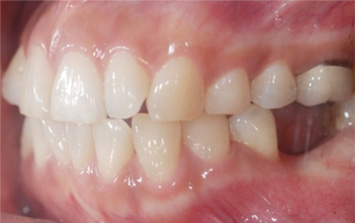

오른쪽 앞니 상실로 내원한 환자분. 앞니의 상실로 치아 사이 틈이 넓어지고 있어 교정으로 임플란트 식립 공간을 만든 후

임플란트 식립을 하였습니다. 앞니가 상실된 기간이 길어 교정치료를 하지 않고 임플란트를 식립할 경우

벌어진 치아 사이로 음식물이 끼거나 치아형태 이상으로 문제가 생길 수 있습니다.